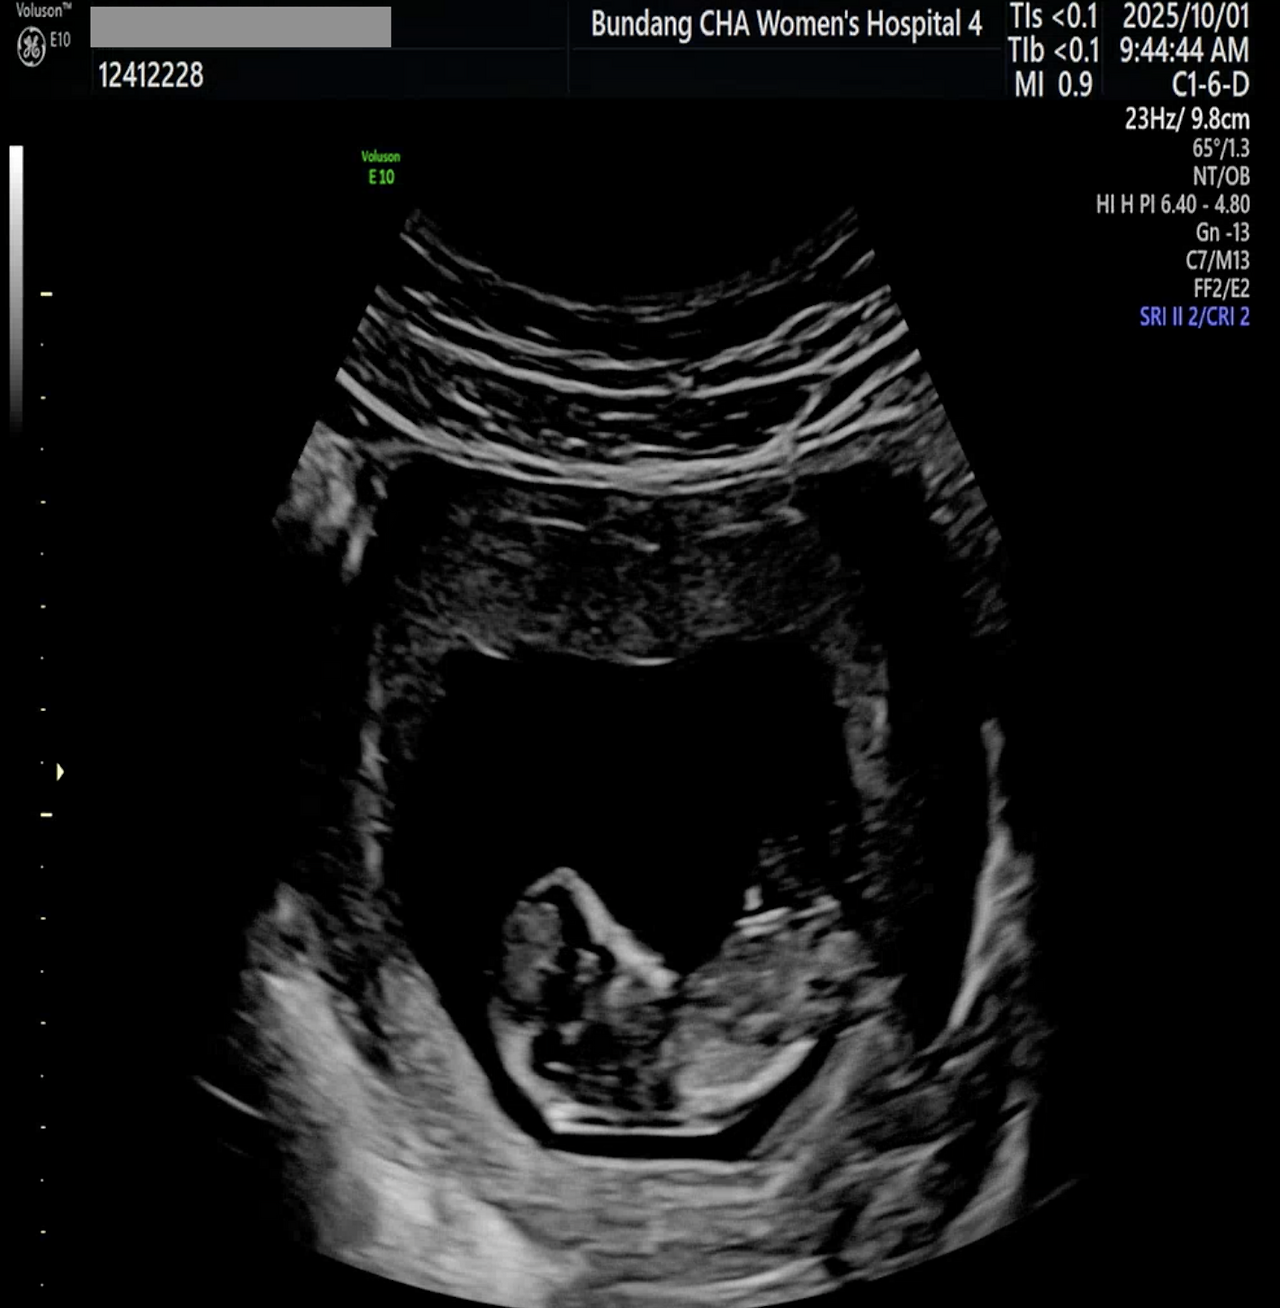

스크린샷 2025-10-12 오전 12.56.27.png 젤리곰을 벗어나서 어엿한 태아가 된 우리 아이